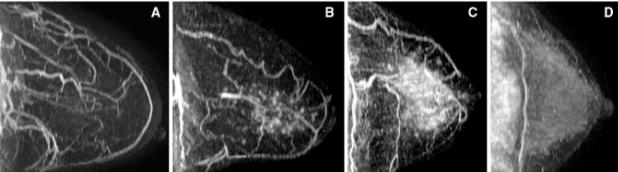

Khi hình ảnh cộng hưởng từ vú (MRI) trở thành một phương thức được chấp nhận rộng rãi hơn để sàng lọc ung thư vú ở những phụ nữ có nguy cơ cao thì tình trạng hormone và chu kỳ kinh nguyệt là những cân nhắc hình ảnh quan trọng.

Trong đa số trường hợp chụp MRI vú, việc sử dụng thuốc đối quang (hoặc tương phản) từ khá phổ biến. Vì thuốc đối quang từ góp phần rất lớn trong việc xác định và phân loại tổn thương dựa vào sự khác biệt ngấm thuốc so với mô nền cũng như tính chất bắt thuốc của chúng.

Thời gian lý tưởng cho MRI của vú là khoảng giữa ngày thứ năm và 15 của chu kỳ kinh nguyệt. Vì trong giai đoạn hoàng thể của chu kỳ kinh nguyệt (từ ngày thứ 15 trở về sau), với sự gia tăng hormone Estrogen và Progesterone gây ra tình trạng phù nề và phát triển thùy tuyến. Điều này dẫn đến sự tăng ngấm thuốc mô vú trong giai đoạn hoàng thể của chu kỳ kinh nguyệt, trong đó tối đa bảy ngày trước khi có kinh nguyệt. Do đó, MRI vú không nên được thực hiện trong thời gian này, mà thay vào đó, giữa ngày thứ năm và 15, đủ lâu sau giai đoạn hoàng thể để giảm bất kỳ sự ngấm thuốc mạnh mô nền gây dương tính giả.

Một hạn chế của MRI vú ở phụ nữ tiền mãn kinh là sự dao động Nội tiết tố trong chu kỳ kinh nguyệt đã gây ra tình trạng tăng ngấm thuốc của gadolinium trong mô vú bình thường khiến việc đánh giá hình ảnh MRI trở nên khó khăn hơn.